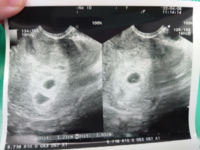

胎児の姿を初めて見たとき!産婦人科で心音を聞いている動画もご紹介します。編集:てれにゃん撮影機材Canon EOS M6 Mark II https//amznto/36xBPjx エコー写真を見てもわかるように 胎嚢の形もいびつ ですし。 胎嚢が成長をしていれば大きい小さいは流産とは関係ないようですが、やはり胎嚢の形がいびつなのはよくないようです。 2度目の妊娠 前回の妊娠から四年後に再び妊娠をしました。

4週 胎嚢 エコー写真- 妊娠9週はエコー検査で分娩予定が決まる時期です。 胎芽であった赤ちゃんがヒトの形へ成長しエコー検査で胎児心拍の確認ができる頃でしょう。 この記事ではエコーで分かる胎児の様子とダウン症、そしてNIPT (新型出生前診断)についてを医師が解説し 妊娠5週6日目のエコー写真と胎嚢の大きさ&費用 妊娠5週6日目のエコー写真と胎嚢の大きさ ↓↓ 胎嚢(GS)は、143mm で 前回受診時(妊娠4週5日目)のときよりも大きくなっていました!!

12週〜17週の双子エコー写真どっちがどっちか分からない時期 18週の双子エコー写真性別と位置、大きさがはっきりしてくる時期 22週の双子エコー写真双子の逆子が常になった時期 26週以降の双子エコー写真顔だけでもはみ出てしまう時期 病院では、尿検査とエコー検査で妊娠の確認を行いますが、エコー検査の際には下記の3つのポイントに注視して妊娠確定をしています。 では、3つのポイントをみてみましょう。 ①子宮内の胎嚢確認 まず、子宮内に胎嚢(たいのう)が確認できるかチェック。 訳あって、5週2日のときに 他院でエコーをしたら、うつりは胎嚢は真っ黒でまん丸でした。 ですが、その2日後、いつもの病院でエコーを見ると うつりが非常に不鮮明でかなり不安です。 ぼやけてみえる・ゆがんで見えるのは流産の兆候と よく聞きます

結論: 6w0dで心拍確認できた人の割合は 72% でした 出産に至った46人中、6w0dのエコーで心拍確認済みとなったのは33人でした。 前日の5w6dではもっと少なかったので、この1日で赤ちゃんが随分成長したことになります。 5w6d胎嚢の大きさは平均144mmエコー写真では、GS (gestational sacの略)と表記されます。 一般的に、胎嚢は妊娠4週後半~5週頃にかけて確認することができるとされています。 通常は、胎嚢・胎芽・心拍の三つを確認できた時点で、正常妊娠であると診断されます。 ただし、胎嚢が確認 タイトルの空っぽの胎嚢のエコー写真。 私、はじめての胎嚢確認の時にはじめてエコー写真をもらって 最初はブログに載せようかと思ったのですがやめました。 なぜなら、私が陽性判定ももらえず、陰性の日々が続いた時 人のエコー写真を見るのが

胎嚢が小さくて不安でたまらない方へ。 5w0d時のエコー写真です。 5wで胎嚢3ミリ先生からは何も言われなかったものの、小さくてとても不安で検索魔になっていました。 しかし目に入ってくるのは良くない結果だったという情報ばかり。 これがこの時もらったエコー写真です。子宮だけ写ってる。。 一般的には、4週後半から5週前半に胎嚢が確認でき、5週後半から6週前半で胎芽や心拍の確認ができる そうです。 となると、5週2日の私は胎嚢が確認できるはずだったのですが。